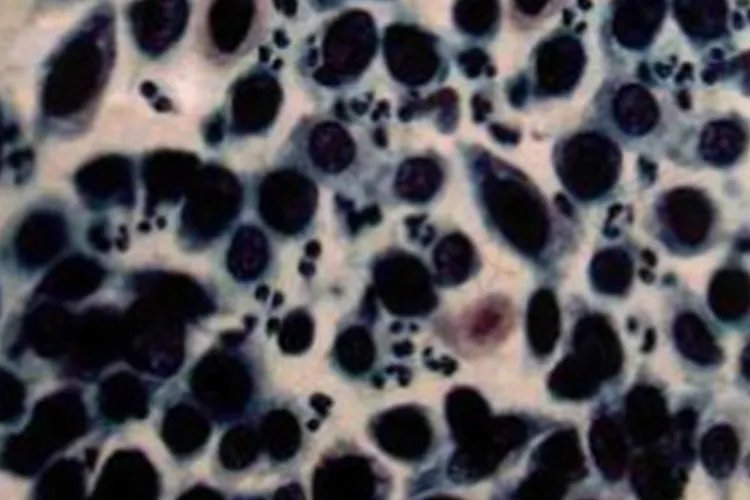

低分化鳞癌癌细胞以中、底层细胞为主,细胞分化程度低。表现为胞体小、大小不等,多呈圆形、卵圆形,也可见不规则形

小细胞未分化癌癌细胞排列紧密,多成束出现;胞体小,胞质更少,似裸核,核质比增大显著;核呈不规则的圆形、瓜子形、燕麦形,核染色质粗、不均匀。